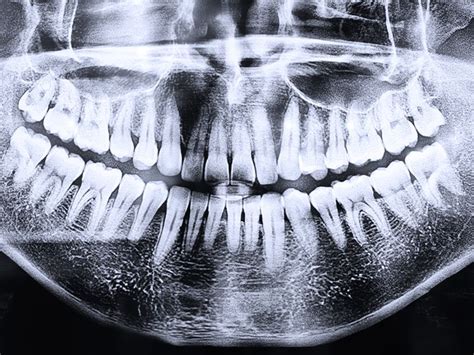

La radiografía panorámica dental es una herramienta fundamental en odontología, ofreciendo una vista completa de las estructuras dentales y maxilofaciales.

La radiografía panorámica (también conocida como ortopantomografía dental) se sirve de una máquina especial de rayos X, un dispositivo que gira alrededor de la cabeza del paciente. La radiografía panorámica es una técnica radiológica que muestra las estructuras óseas (los maxilares, la articulación de la mandíbula y los dientes) del rostro del paciente en una sola imagen general. Para ello, se vale de una máquina de rayos X especial, que rota alrededor de la cabeza del paciente.

Esta radiografía es especialmente útil en la detección de caries y quistes y en la evaluación de la posición de los dientes. Su principal ventaja la encontramos a la hora de realizar un examen visual global de la dentadura para detectar infecciones y malformaciones en la estructura ósea.